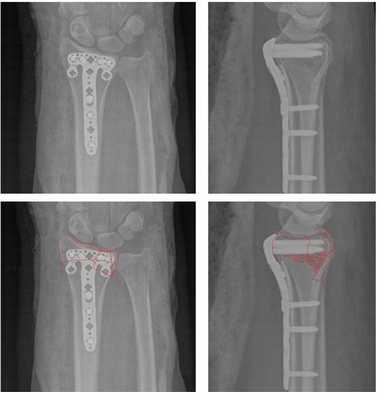

Рис. 1. Внутрисуставной нестабильный перелом лучевой кости.

Рис. 2. . тот же перелом после закрытой репозиции (полного сопоставления отломков нет).

Рис. 3. Рентгенограмма кистевого сустава через 5 месяцев после травмы: имеется внутрисуставное смещение, деформация сустава.

До операции:

После операции:

После операции